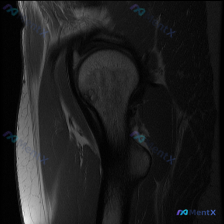

这份右肩部MRI病例,用户关注盂唇病变但影像提示另有问题?

最近整理了一份右肩部MRI的病例资料,是冠状位T1加权图像。用户最初关注的是盂唇病变(Labral pathology),但影像分析有几个有意思的发现:

- 冈上肌肌腱远端(接近肱骨大结节止点)信号异常增高,形态大致连续

- 肱骨头骨髓内可见多个圆形/椭圆形低信号影(软骨下囊肿),周围有轻微骨硬化

- 肩峰形态、肩峰下间隙大致正常